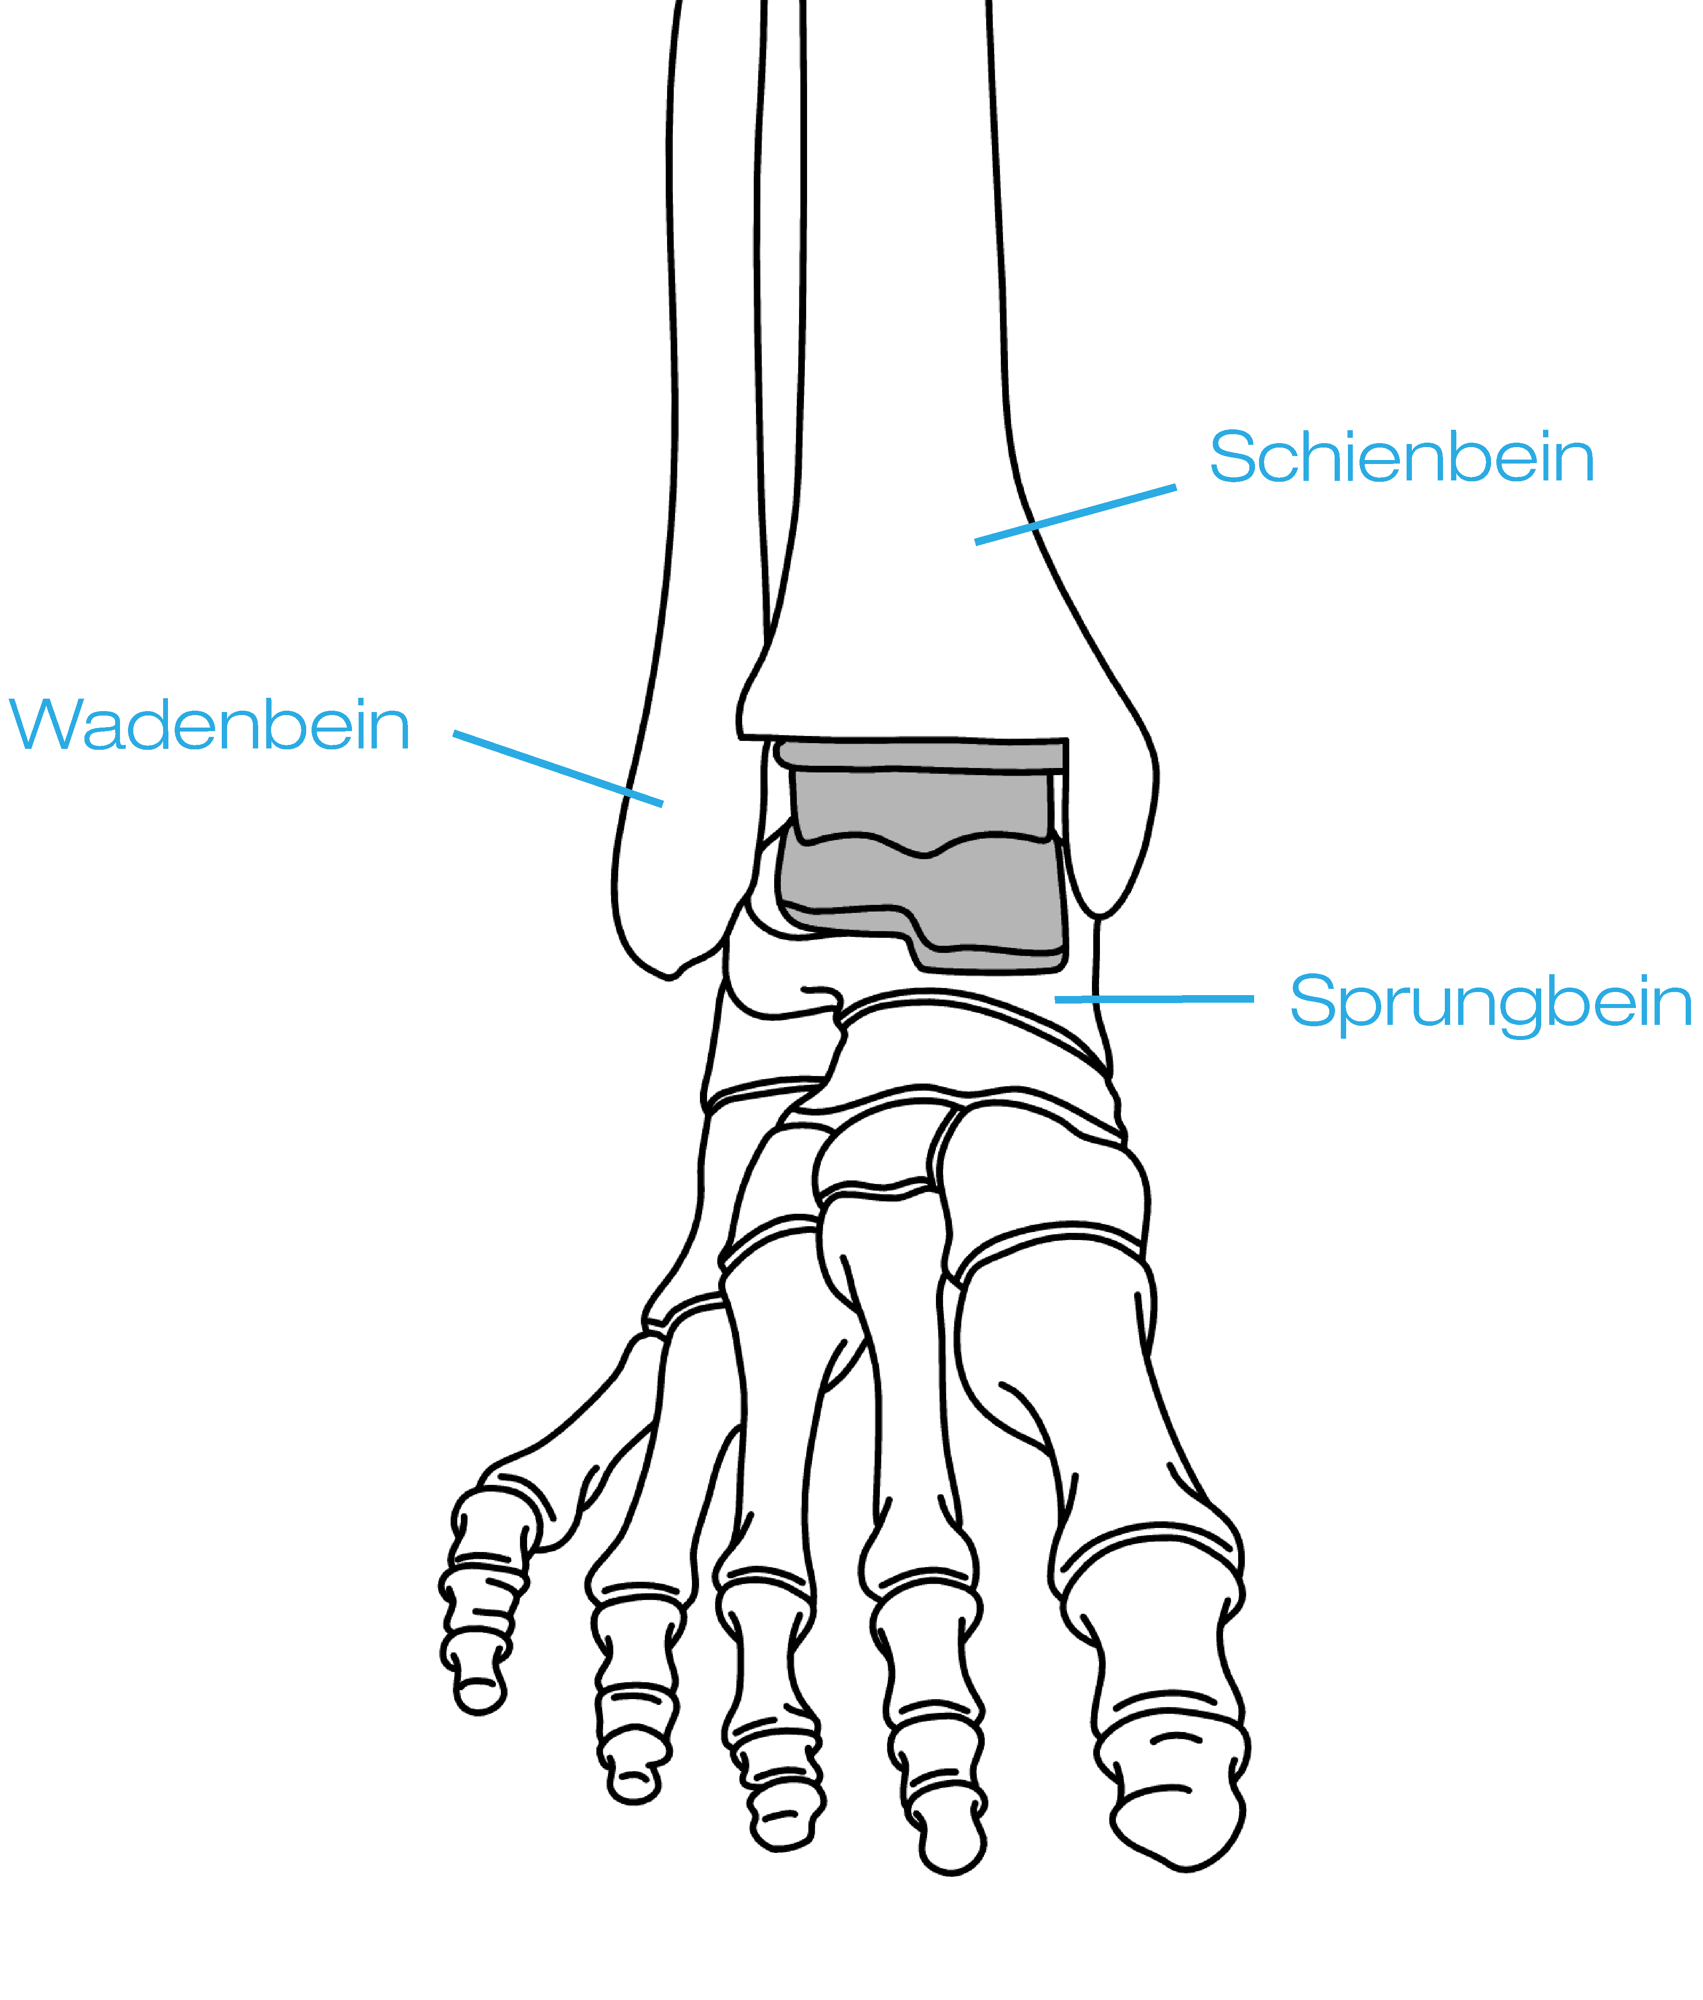

Grundlegend kann bei der Ursache der Arthrose im Sprunggelenk zwischen primärer und sekundärer Sprunggelenksarthrose unterschieden werden. „Die Ursache von sekundärer Arthrose im Sprunggelenk ist in vielen Fällen ein verjährter Bruch im Sprunggelenk. Man spricht hier auch von einer posttraumatischen Arthrose“, so der Arthrose Experte Prim. Dr. Norbert Freund. Sprunggelenksarthrose kann aber auch durch Fehlbelastungen und unbehandelte Fehlstellungen auftreten. In solchen Fällen spricht man von einer primären Sprunggelenksarthrose. Solche Fehlstellungen können zum Beispiel Plattfüße oder auch O oder X-Beine sein. Deutlich häufiger als das Sprunggelenk, sind Hüfte sowie Knie von Arthrose betroffen.

Der Krankheitsverlauf von Arthrose im Sprunggelenk passiert in der Regel schleichend. Sind die Symptome im Anfangsstadium kaum bis gar nicht spürbar, können die Symptome bei fortgeschrittener Sprunggelenksarthrose massive Schmerzen und Schwellungen auslösen. Bei der posttraumatischen Arthrose im Sprunggelenk, kann es vorkommen, dass erst 10 Jahre nach dem Unfall Symptome auftreten. Anzeichen auf eine fortschreitende Sprunggelenksarthrose sind tiefgehende Schmerzen sowie deutliches Ziehen im Bereich des Sprunggelenks.

Auch Belastungsschmerzen nach längeren Spaziergängen oder Wanderungen können auf eine Arthrose im Sprunggelenk hinweisen. Bei anhaltenden Schmerzen im Sprunggelenk sollten Sie jedenfalls einen Orthopäden aufsuchen, um die Ursachen Ihrer Schmerzen abzuklären. Eine frühzeitige Therapie, konservativ oder operativ ist ausschlaggeben für Ihr persönliches Wohlbefinden.